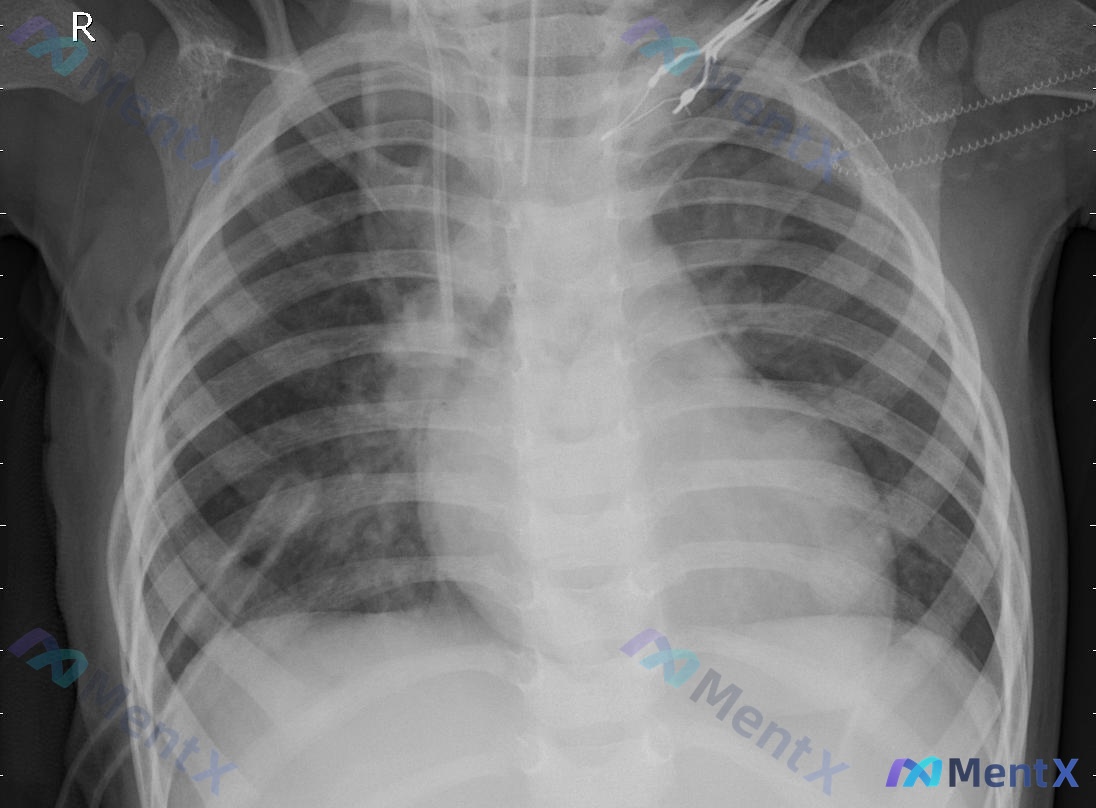

这个气管插管的幼儿胸部X光片,真的只是支气管肺炎吗?

整理到一份幼儿/新生儿的胸部X光正位片资料,临床背景是重症监护、已气管插管。 先把影像表现放出来: - 投照是前后位(AP位),吸气相欠佳,双侧膈肌位置偏高 - 气管插管尖端在隆突上1-2cm,位置适中;纵隔增宽考虑生理性胸腺影 - 双肺纹理增多、增粗、模糊,呈网格状及斑片状影,双中下野明显;右肺上...